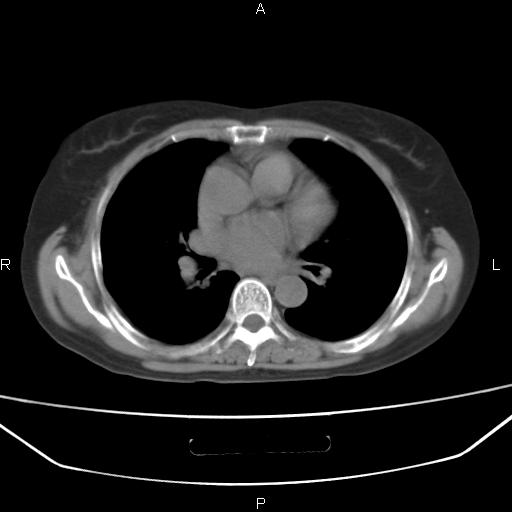

考虑:右肺上叶周围型肺癌(分叶状肿块+砂粒状钙化+胸膜尾征)。

病灶见明显分叶、大小较大(大于3cm?),老年人,多考虑:肺癌,建议穿刺活检。

典型的中心型肺癌,尖段支气管阻塞。

周围性肺癌,

右肺上叶周围型肺癌可能性大。

考虑:右肺上叶周围型肺癌